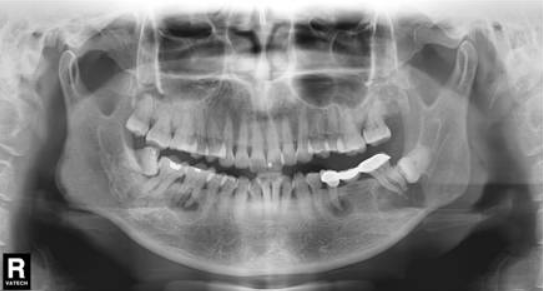

牙医需警惕:一张牙片,“救”了诊所,也救了患者!